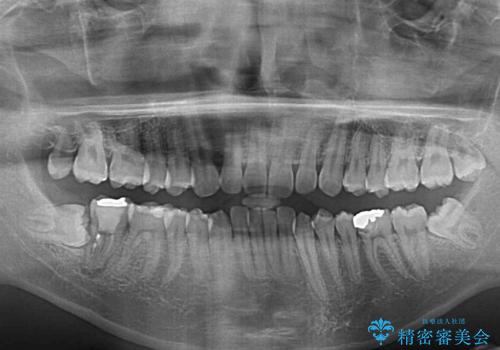

- 口元の突出感を治したいとのことで来院された患者様です。

上下顎ともにIPR(歯と歯の間を削る)と歯列全体の拡大によって口元が引っ込むように設計し、インビザラインにより治療を行うこととしました。

抜歯をして口元を下げなければならないほど出っ歯ではなかったため、少しずつ治療ゴールを変更しながら仕上げていきました。